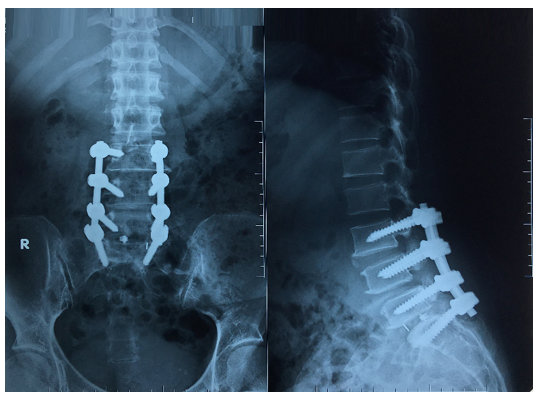

Tái khám sau 1 tháng, các triệu chứng đau thắt lưng và đau rễ thần kinh cải thiện đáng kể. Xquang sau 1 tháng cho thấy phương tiện đúng vị trí (Hình 3)

Hình 3. Xquang cột sống thắt lưng sau phẫu thuật 1 tháng. Phương tiện kết hợp xương L3, L4, L5, S1

Hình 2. Xquang cột sống thắt lưng sau phẫu thuật 3 ngày. Phương tiện kết hợp xương L3, L4, L5, S1.